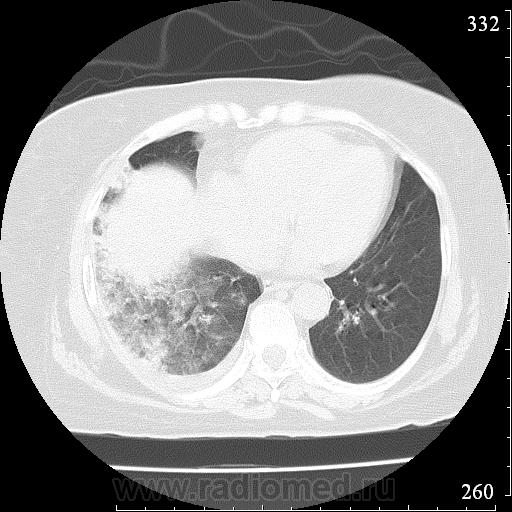

Еще один случай диагностики ТЭЛА методом КТ-ангиографии у женщины 59 лет. Основная клиническая жалоба - выраженная одышка. Определяется: полный дефект наполнения в системе правой ЛА (бифукация и нижнедолевая), неполный дефект наполнения в левой ЛА (нижнедолевая), пристеночные тромбы по задней стенке в области бифуркации обеих легочных артерий. Инфаркт (массивное кровоизлияние) нижней доли правого легкого. Правосторонний малый (120см3) гидроторакс. Несмотря на выраженные тромбы, поперечники легочных артерий - в пределах нормы.; на нативной (безконтрастной) КТ - тромбы не видны. Несмотря на почти полный дефект наполнения в левой нижнедолевой артерии, изменений в легочной ткани левого легкого нет. Также приводится топограмма, как вариант, приближенный к рутинной рентгенограмме